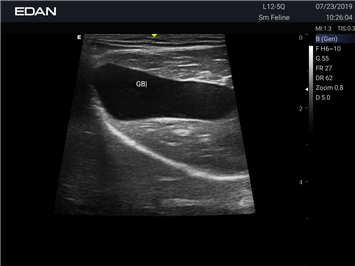

EDAN Acclarix AX2 VET

Ветеринарный ультразвук одним нажатием. Система Acclarix AX2 VET разработана с целью обеспечить бескомпромиссную производительность по доступной цене. Наличие уникальных двойных аккумуляторов в легком корпусе массой 4,5 кг из магниевого сплава позволяет системе Acclarix AX2 VET удовлетворять все потребности ветеринарных исследований, сохранив низкую стоимость.

EDAN Acclarix AX2 VET представляет собой специализированную ветеринарную ультразвуковую систему, сочетающую высокую производительность с доступной ценой. Благодаря продуманной конструкции и передовым технологиям, система обеспечивает качественную диагностику животных различных видов.

B-режим, Двухмерное сканирование:

Да